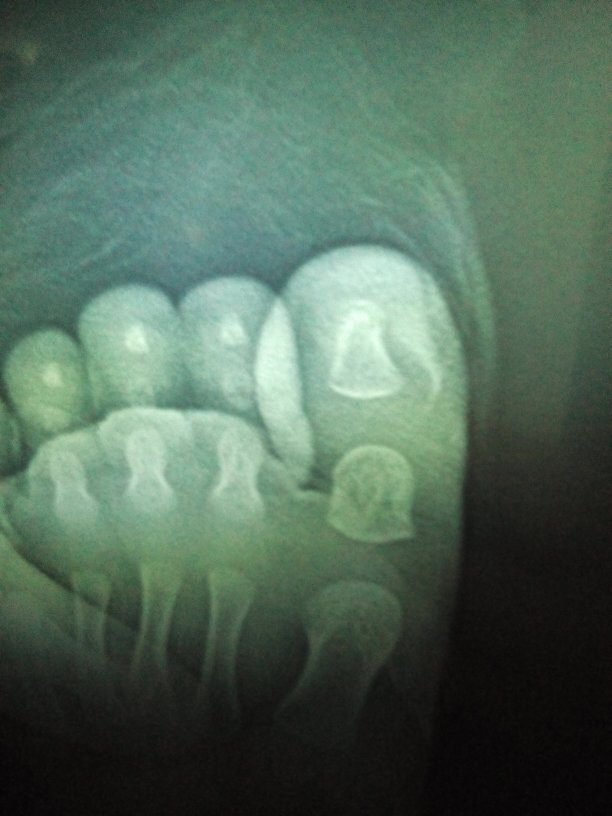

孩子脚趾被砖头砸到了,拍片后诊断结果为趾甲粗隆骨折,趾软组织损伤。请问这种情况严重吗,影响以后发育和走路否?刚一岁。

病情分析:如果出现趾甲粗隆骨折原细敢则上来说是必须采取手术治疗的,可以使用手术将钢钉固定在骨折的部位,然虏径趋后同时用外墙板进行固定,这期间尽量不要则怪走路, 指导意见:如果不采取外固定的话,很可能骨折部位不能够正常的连接,会出现活关节,甚至出现骨折错位错位的情况,平时一定要多补钙片,这样有利于钙质的吸收,能够加快骨折的愈合,